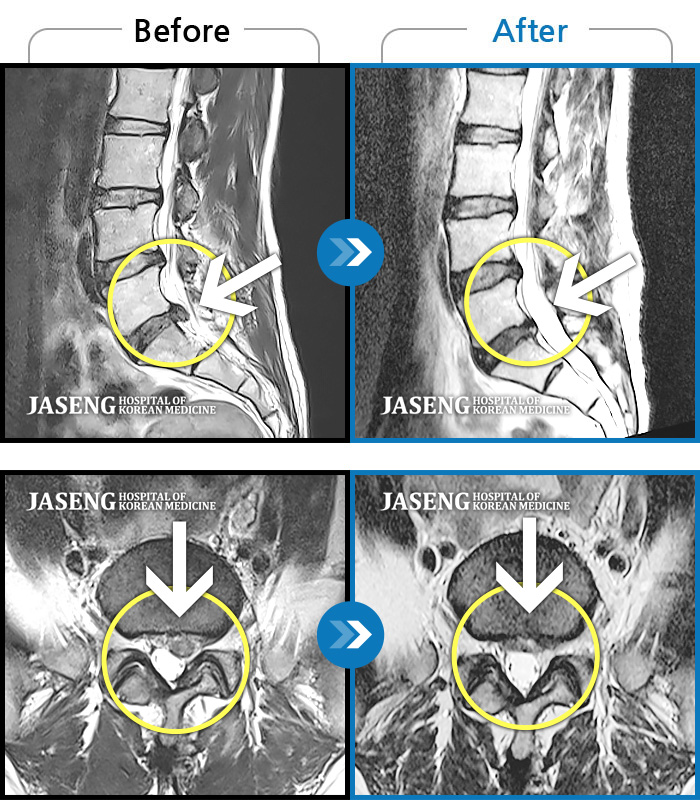

ȯںп Ǹ ǿ ԿǾ, ο ġ ۿ Ƿ ġḦ Ͻñ ٶϴ.